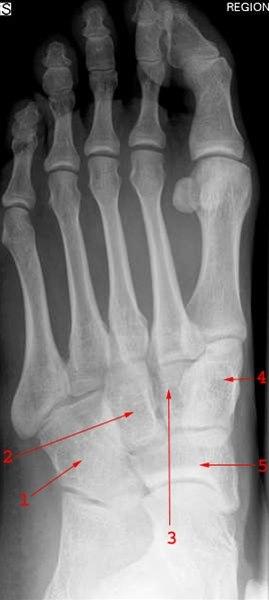

Diagnosen

Plattfot påvises ved undersøkelse av føttene. Den indre fotbuen siger ned mot underlaget når foten belastes. Ved den vanlige myke plattfot får foten normal fasong når trykket avlastes, som for eksempel når man står eller går på tærne. Dette i motsetning til stiv plattfot der foten alltid er flat, for eksempel på grunn av sammenvoksninger mellom ben i foten.

Røntgenundersøkelser er ikke nødvendig ved plattfot annet enn i de tilfellene hvor det foreligger stiv plattfot og pasienten plages med smerter.